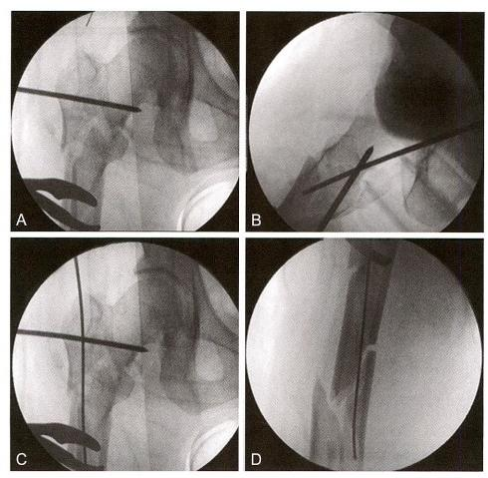

(3)第三步:插入导针、推顶骨块。

在复位手指引导下插入导针(图12-5A) 。 在复位手指配合下,透视 确定需要推顶的部位(图12-5B) 。 顶棒技术:经皮插入克氏针,推顶移 位骨块(图12-5C), 并将导针插入中间骨块髓腔(图12-5D)。 采用同样 方法,用克氏针推顶远端骨块,并插入导针(图12-5E 、F)。

图12-5 插入导针及推顶骨块。 A. 插入导针;B. 透视确认需要推顶的位置;C. 推 顶复位骨块;D. 将导针插入中间骨块;E. 撬拨复位远端骨块;F. 导针进入远端髓腔;G. 近端骨块复位情况;H. 远端骨块复位情况

扩髓后插入髓内钉并行上、下锁定固定(图12-5G), 从皮钉可以看 出,均在微创闭合复位下进行(图12-5H)。